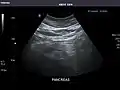

Left kidney